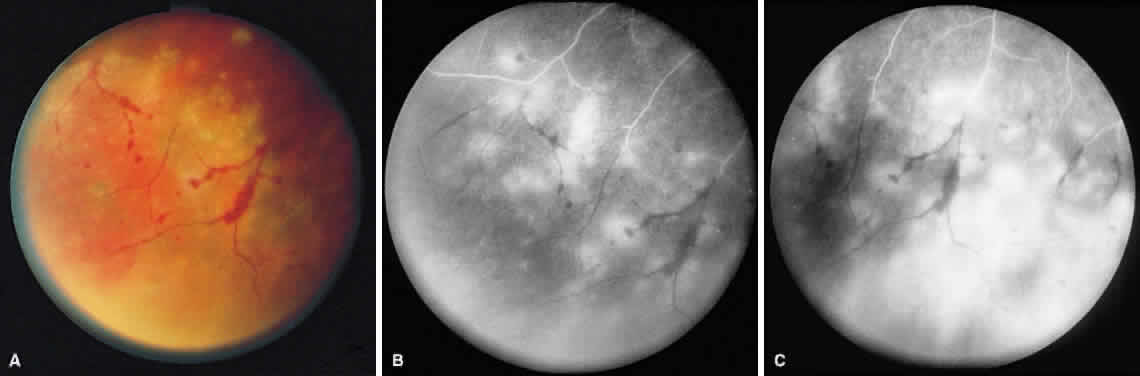

ARN is characterized by a retinal vasculitis affecting both the arteries and veins in the fundus, which is manifested by sheathing of the larger vessels (Fig. 2).7–10,16 Initially, patchy areas of peripheral retinal whitening (“thumbprint lesions”) representing full-thickness retinal necrosis are present or develop shortly after the vasculitis (Fig. 3). During a course that may span days or weeks, these patches coalesce into geographic areas (Fig. 4A). The entire peripheral retina (360 degrees) may be involved, or, more commonly, there are several noncontiguous patches of necrosis, each covering from a half to three clock hours (Figs. 5 and 6). The posterior segment lesions may not be detected without examination of the peripheral retina.

Fig. 4. A. With progression of ARN, the areas of retinal whitening begin to coalesce. Mild perivascular retinal hemorrhages are noted. B. Fluorescein angiography in the venous phase reveals retinal vascular nonperfusion in areas of active retinitis. C. In the late-phase angiogram, fluorescein hyperfluorescence is seen in areas of retinitis and around the retinal vasculature.

Intravenous fluorescein angiography may be helpful in delineating the extent of infection and elucidating the cause of central visual loss. In the early frames, choroidal perfusion defects may be seen; these defects are caused by areas of focal choroidal inflammatory cell accumulation and overlying retinal pigment epithelial damage (Fig. 16). Such choroidal perfusion defects may occur away from zones of active necrosis.42 Acute obstruction of the central retinal artery or any of its branches may be present. Peripheral views in the areas of active retinitis commonly show little or no intravascular fluorescein in the retinal arteries and veins. Often an abrupt “cut-off” of the intravascular fluorescein may be apparent at the edges of the retinal inflammation (see Fig. 4B and C). Areas of active retinitis show blockage of the underlying choroidal fluorescein pattern (see Fig. 7B). Recirculation phase views may reveal macular leakage, optic disc, and retinal vasculature staining.